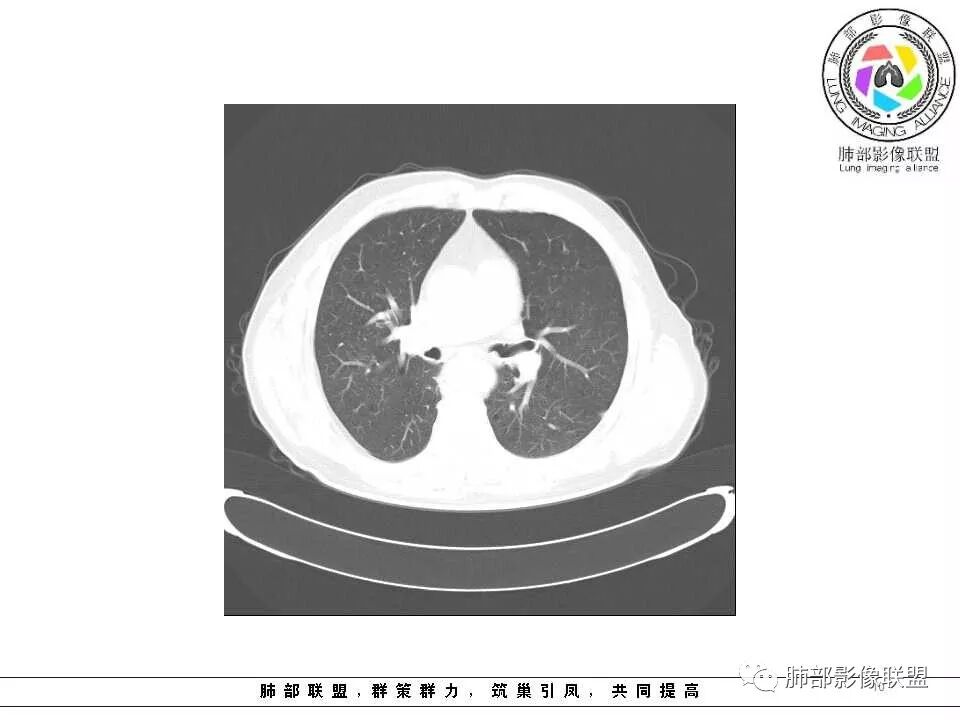

老年男性,左肺舌段见多个小结节灶及斑片状高密度灶、磨玻璃影,结节灶边界清晰,光滑,无明显分叶,密度均匀,周围病灶密度不均,一年内生长,考虑恶性肿瘤并阻塞性肺炎出血,小细胞可能大。

老年男性,肺气肿基础。约一年时间出现左肺上叶舌段支气管近端结节影,远端斑片样阴影,边缘模糊。考虑近端恶性占位,远端有阻塞性炎症。

老年男性,两肺可见小叶中央型肺气肿,提示应该有抽烟史。2016年片,右肺门支气管稍模糊,考虑慢性感染,纵膈淋巴结稍大。但2017年左肺上叶新发占位,堵塞支气管,引起局部肺不张伴感染,且纵膈淋巴结较2016年变大,患者同时伴有咯血,考虑恶性。鳞癌?类癌?小细胞?

老年男性,有咳血病史,左肺上叶舌段一年时间出现新发类圆形小结节,感觉在支气管内,部分凸出气管外,没有mpr不好说,远端肺野斑片模糊影,考虑阻塞性炎症,纵隔无明显肿大淋巴结,小细胞代排,按照发展速度,类癌低度恶性,应该发展缓慢,一年病史,代排,首先考虑鳞癌并阻塞性炎症

肺气肿背景,2016年左肺上叶上舌段见微结节,2017年5月左肺结节增大,密度均匀,边缘光滑锐利,与邻近血管关系密切,血管贴壁走行,外侧见尖状突起,下舌段片状影,沿着支气管走行,内有粘液栓,考虑鳞癌,鉴别小细胞肺癌。

肺气肿背景,左肺上舌叶结节一年复查明显增大,边缘光滑。下舌叶片状影,界限模糊。考虑上舌叶小细胞癌并下舌叶感染。鉴别鳞癌

肺气肿背景,2016年左肺上叶上舌段见微结节,一年后左肺结节增大,密度均匀,边缘光滑、膨隆,似见小分叶,下舌段片状影,沿着支气管走行,内,老年患者,咯血1月。考虑恶性病变并阻塞性肺炎,鳞癌?注意鉴别结核。

老年男性,咯血1月,肺气肿背景,16年左肺上叶舌段结节,左肺门疑似淋巴结肿大,呈结节感。17年左肺上叶舌段见沿支气管走行分布结节 远端阻塞性肺炎,左肺门淋巴结肿大明显,首先考虑恶性病变,鳞癌?类癌?

老年男性,肺气肿背景,左肺上叶舌段一年前小结节后长大,实性,与邻近气管关系密切,远端有少许小片状炎症类小结节状,左肺门淋巴结肿大,首先考虑恶性,鳞癌可能性大,代排小细胞癌。病灶下方斑片状影,考虑炎症。

老年男性,肺气肿背景,对比前片,左肺上叶舌段结节较前进展,周围有斑片状条状密度增高影,左肺门淋巴结肿大,有咯血史抗炎后效果不佳,目测增强强化不好判断,考虑肺癌并阻塞性肺炎可能,鉴别炎症性肺癌,真菌类肺炎,肺脓肿,肺结核,建议完善肿瘤标志物,结核相关检查,病原体检查。

老年男性,咯血一个月,有慢支病史。左肺上叶舌段可见一类圆形结节影,边缘光滑,远端有片条状影,一年前胸ct基本正常。感觉还是考虑肺癌合并阻塞性炎症。鳞癌还是小细胞?